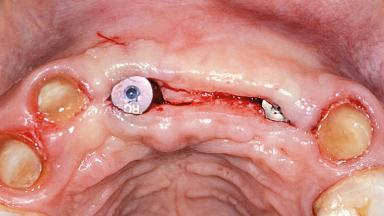

Replacement of Two Central Incisors and One Lateral Incisor with a Fixed Dental Prosthesis on Two Bone-Level Implants

A 38-year-old woman presented with an esthetically unacceptable fixed partial denture replacing teeth 11, 21, 22. She had lost these teeth due to trauma when she was a child. The patient was not in pain but very concerned based on her previous experience that dental treatments had never satisfied her esthetic expectations. She was in good general health and reported no regular medications. No periodontal disease was noted despite the fact that the buccal flange of the prosthesis impeded cleaning of the tooth abutments. The patient did not smoke and complied with home maintenance requirements, as evidenced by her good oral hygiene status.